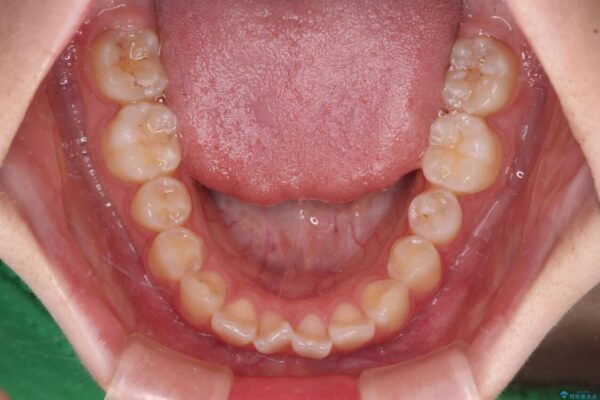

治療前

• インビザラインは使える自信がない ワイヤー装置にて矯正治療 治療前画像

上下前歯のねじれを気にして来院された患者様です。